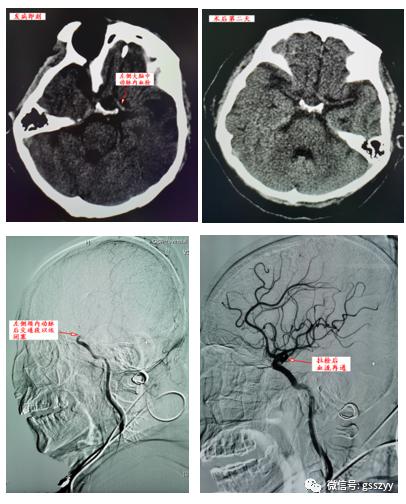

12月3日中午12:30, 83岁高龄的患者文奶奶,因“突发右侧肢体无力,言语欠清2.5小时”就诊于医院急救中心,医生查体后发现,右侧肢体肌力0级,双眼向左侧凝视,急诊颅脑CT未见出血。生命体征:心率33-37次/分,血压150/80mmHg,呼吸18次/分,心电图提示:交界性逸搏,ST段改变。考虑患者有既往2型糖尿病病史,心脏起搏器植入术后25年。NIHSS(美国国立卫生院神经功能缺损评分)评分15分,最终诊断考虑为左侧大脑半球心源性栓塞。

曹骅主任、主治医师赵宏廷做全脑血管造影,发现心源性血栓栓塞于左侧颈内动脉终末端,导致远端不显影,如果不立即拉栓处理,患者左侧大脑半球必将因缺血导致坏死,从而导致肢体功能重度残疾甚至危及生命。向家属交代病情后,立即给予手术,拉出长约10mm×4mm、4mm×3mm新鲜血栓两块。复查造影左侧颈内动脉完全通畅,左侧大脑中动脉、大脑前动脉显影良好。